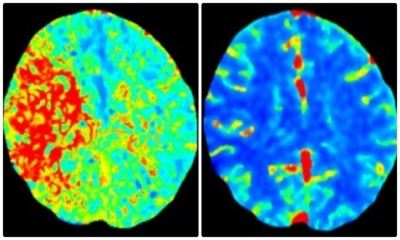

Next up in the fast-moving chain of events was more advanced brain imaging to determine if surgery was required: a CT angiogram and CT perfusion. This color-coded perfusion scan showed the area of Julie’s brain that was inadequately supplied (or perfused) with blood—the red area pictured left. A different but essential view showed that same large area of brain tissue has normal blue color (right). This meant that the red, injured area of her brain could be saved from permanent damage if its blocked blood flow could be emergently restored.